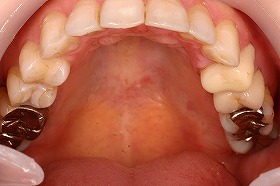

歯の矯正治療 症例ビフォー&アフター

あまり歯のズレが少ないように見える方なのですが、

実は上下の前歯にがたつきがあり、

内側に歯が入り込んでしまっている症例です。

原因としては、あごが小さかったり、

アゴに対して歯が大きい場合など、

歯の生える場所が足りない時に起こります。

この患者様は、非抜歯で矯正治療を進めることができ、

治療後は上下の噛み合わせもよくなりました。